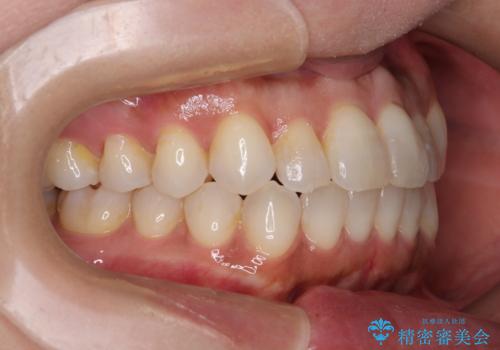

前歯のクロスバイト インビザラインによる矯正治療

- 上下のクロスバイトと前歯のデコボコを気にして来院された患者様です。

インビザラインを用い、IPR(歯と歯の間を削る)と歯列全体を拡大させることで、歯並びを整えていくこととしました。

インビザライン特有の、治療後半に奥歯が咬み合わないという事象が長引きました。

咬み合わないときの対処方法は色々とありますが、ゴムかけなどを活用して噛めるようにしました。